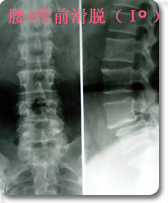

采用后路内窥镜下(XTube)经单侧神经孔腰椎体间融合,椎弓根螺钉复位内固定术,以治疗极外侧腰椎间盘突出(神经孔型)伴腰椎不稳。 优点:通过单侧经神经孔入路途径达到椎间隙,从而达到椎间减压和植骨融合目的。该手术途径单侧入路,显露清楚,不需过度牵拉神经。为外科医生提供了一个能显著减少PLIF手术的很多风险和限制的融合方式。本手术将内窥镜(XTube)与TILIF手术的优点集于一身达到更小的创伤更好的手术效果。 |